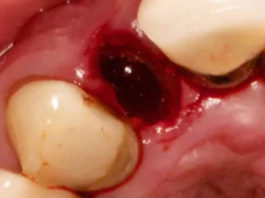

Le gel de chlorhexidine favorise la cicatrisation précoce des plaies après une extraction dentaire, selon une étude